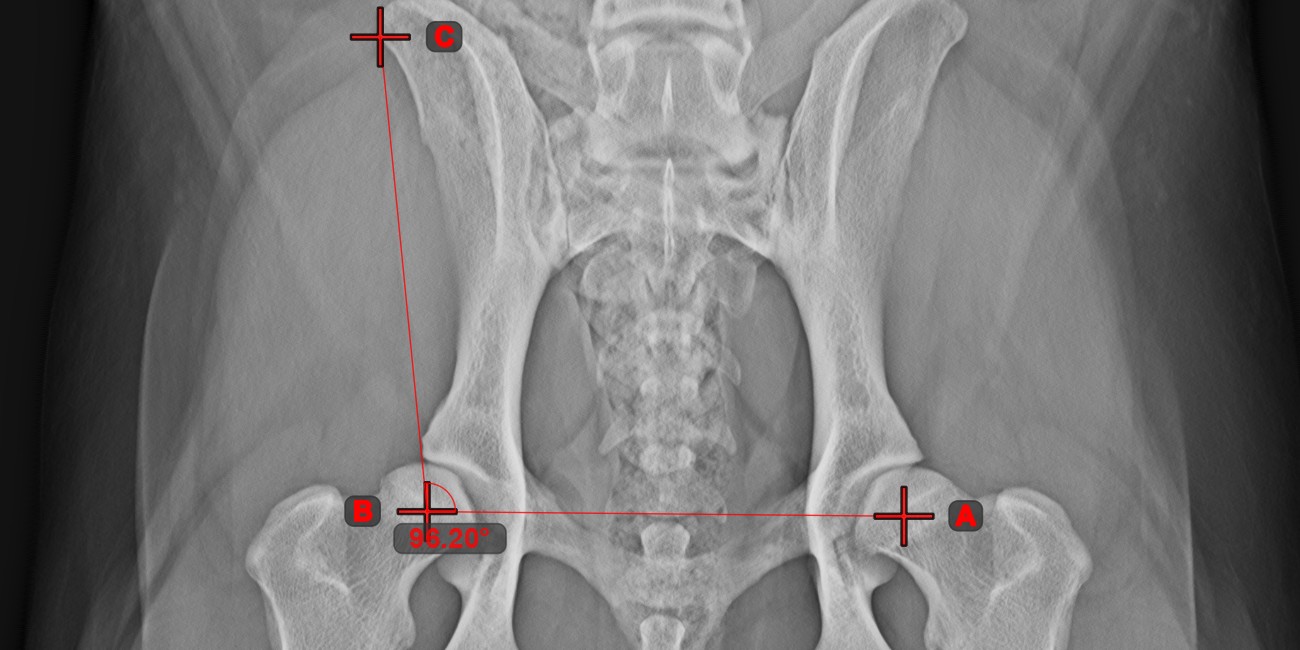

Angle of Lines

../_images/image307.jpg

Calculate the angle between two independent or intersecting lines by using the Angle of Lines tool.

Select the tool from the left toolbar and assign it to one of the available mouse buttons. Start by selecting the first line from the ones already drawn on the scene, or place the start and end points to create the line. Follow the same steps for the second line of the measurement. The angle between the two lines will be automatically calculated.

Modify the start and end points of both lines by using the Select/Move Item tool. The angle between the two lines will be automatically recalculated.

Information

If two lines do not intersect directly, the angle of their extended projections on the scene will be calculated.

../_images/image7.jpg ../_images/image312.jpg